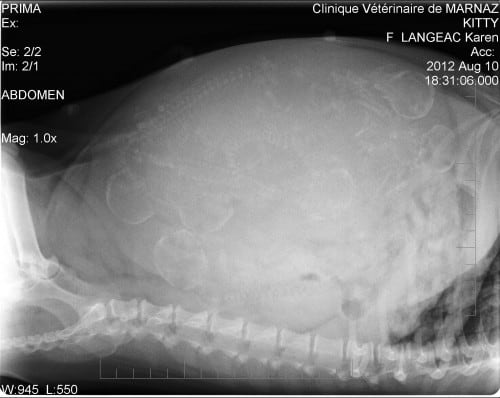

Ce n’est pas 4, ni 5, mais 6 petites têtes que nous voyons. Regardez bien! Kitty nous fait de belles surprises! Category: La vie du sitePar Karen14 août 2012Laisser un commentaire Author: Karen Post navigationPreviousPrevious post:50ème jour….NextNext post:Les chiots 2012